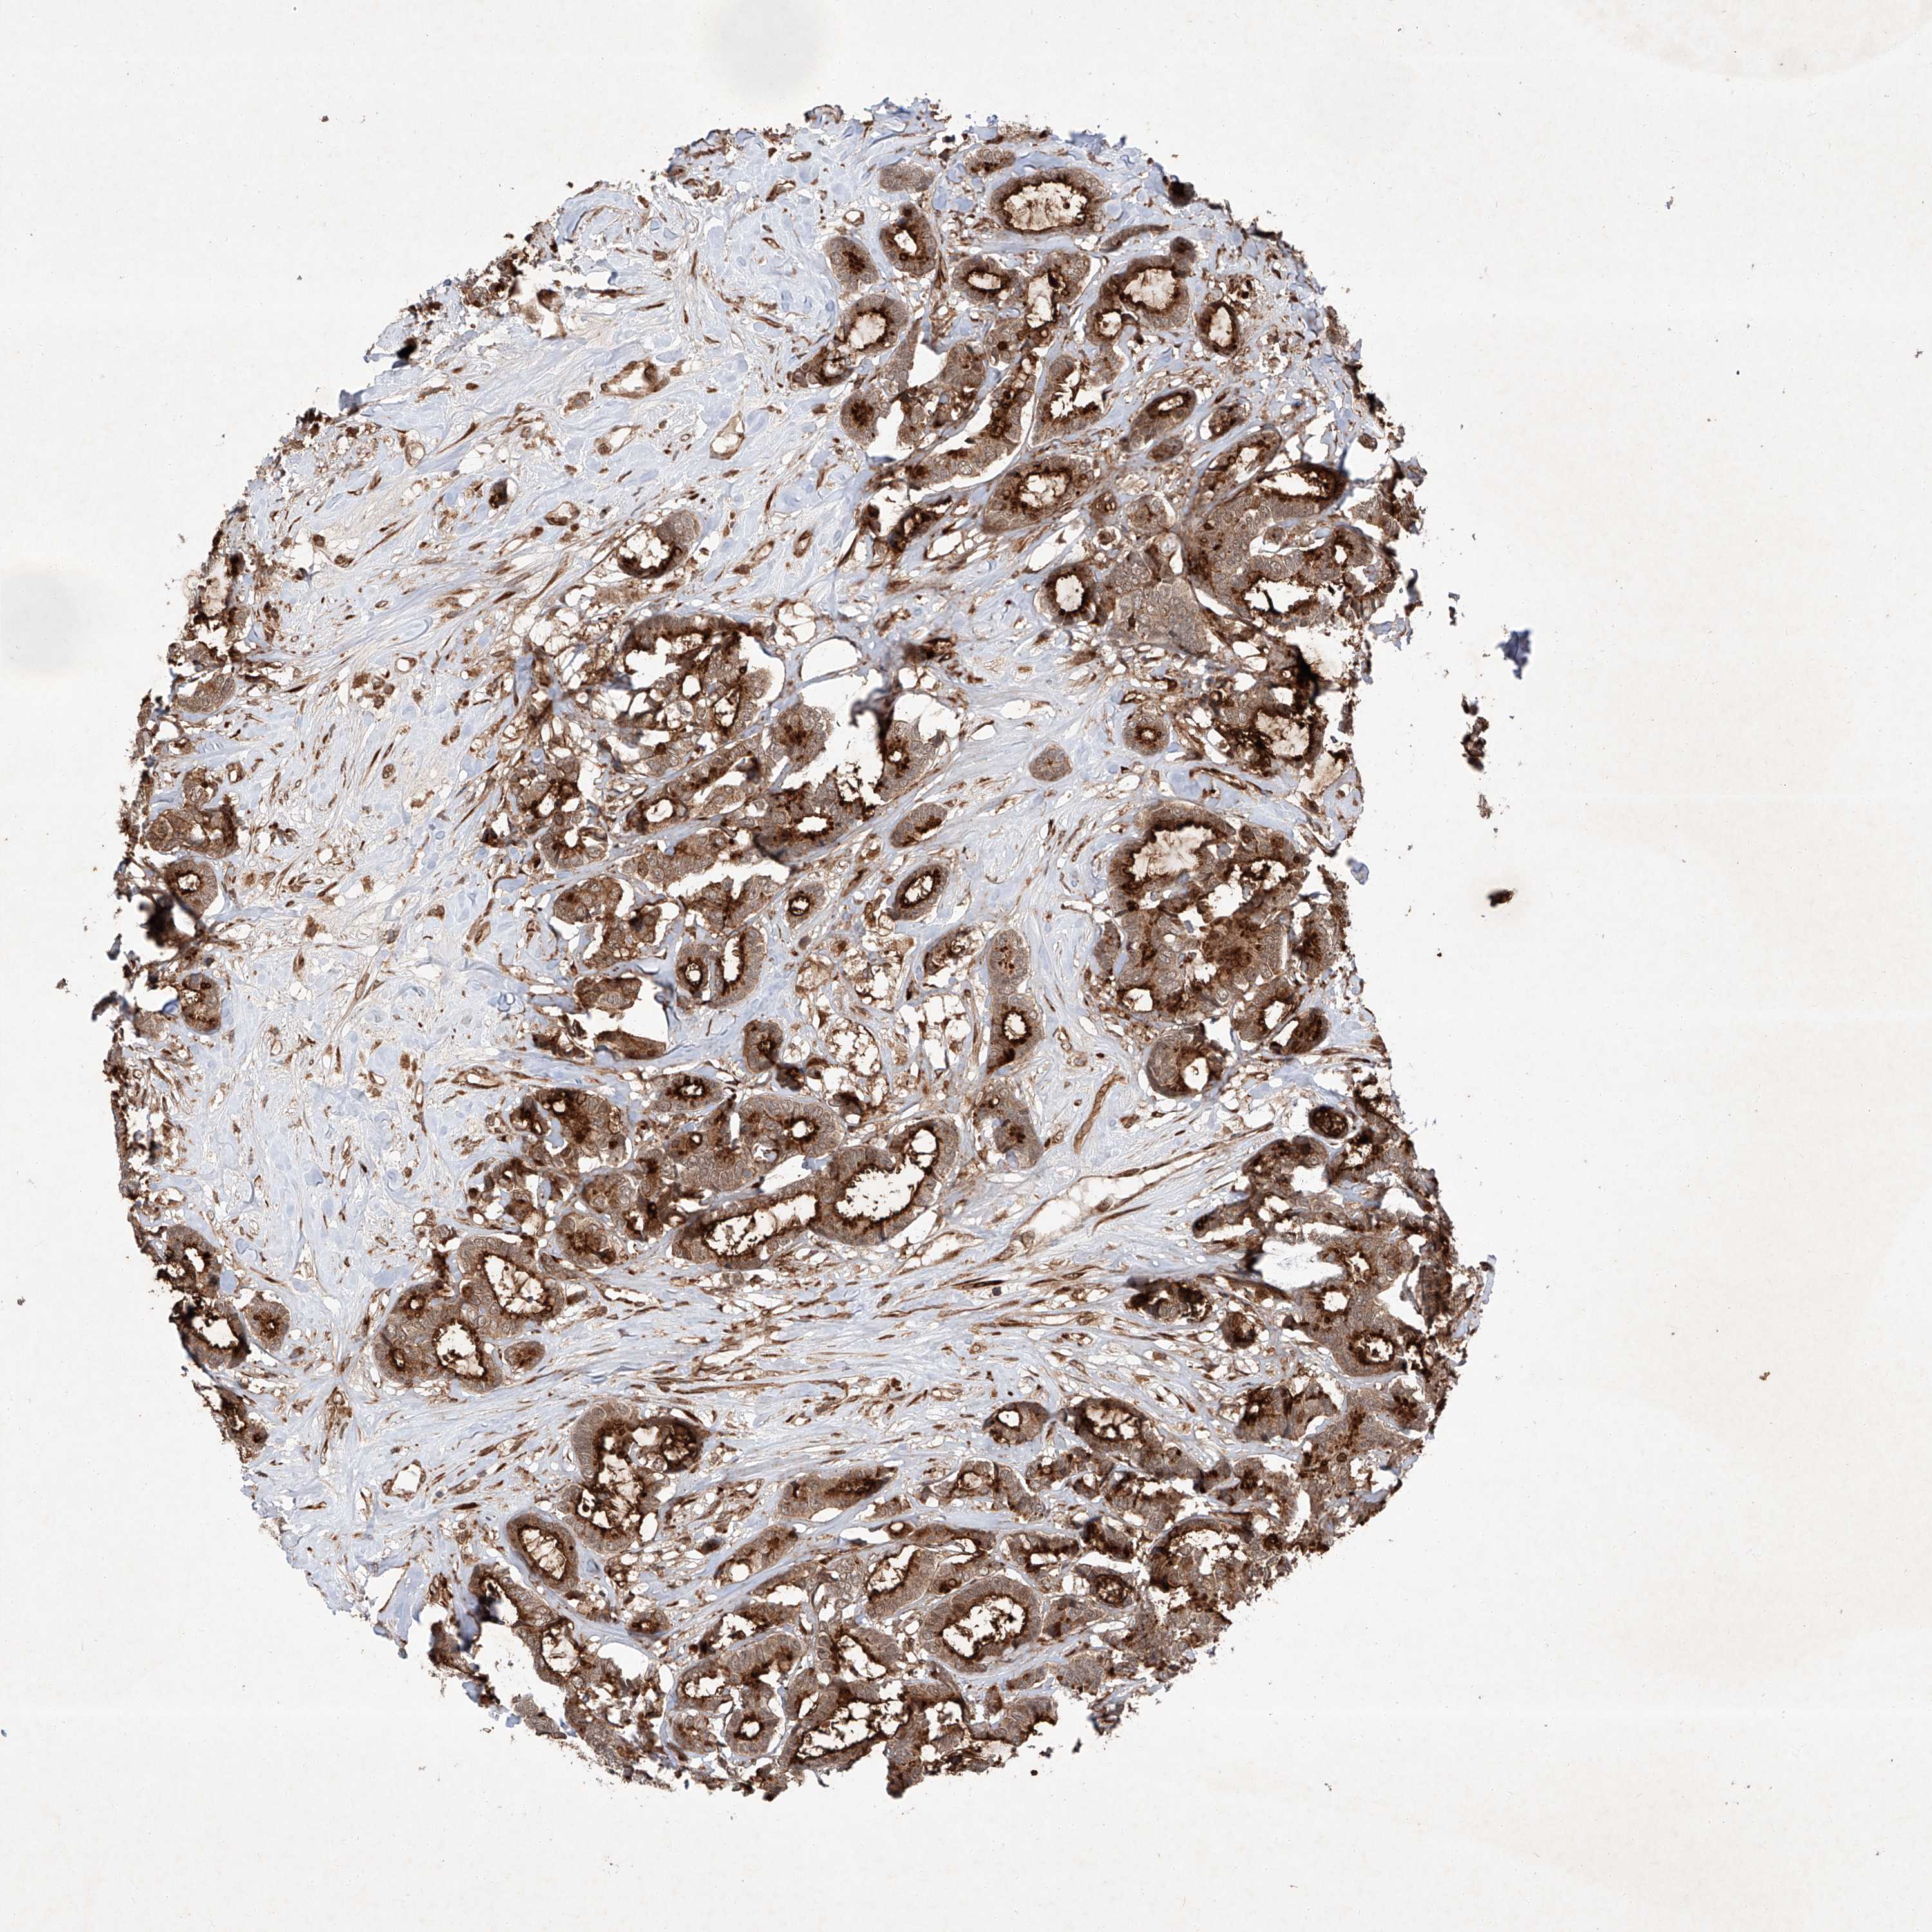

CANCER BREAST CANCER Show tissue menu

BRCA TCGA BRCA VALIDATION PROTEIN EXPRESSION

Breast cancer

Human cancer

Breast invasive carcinoma